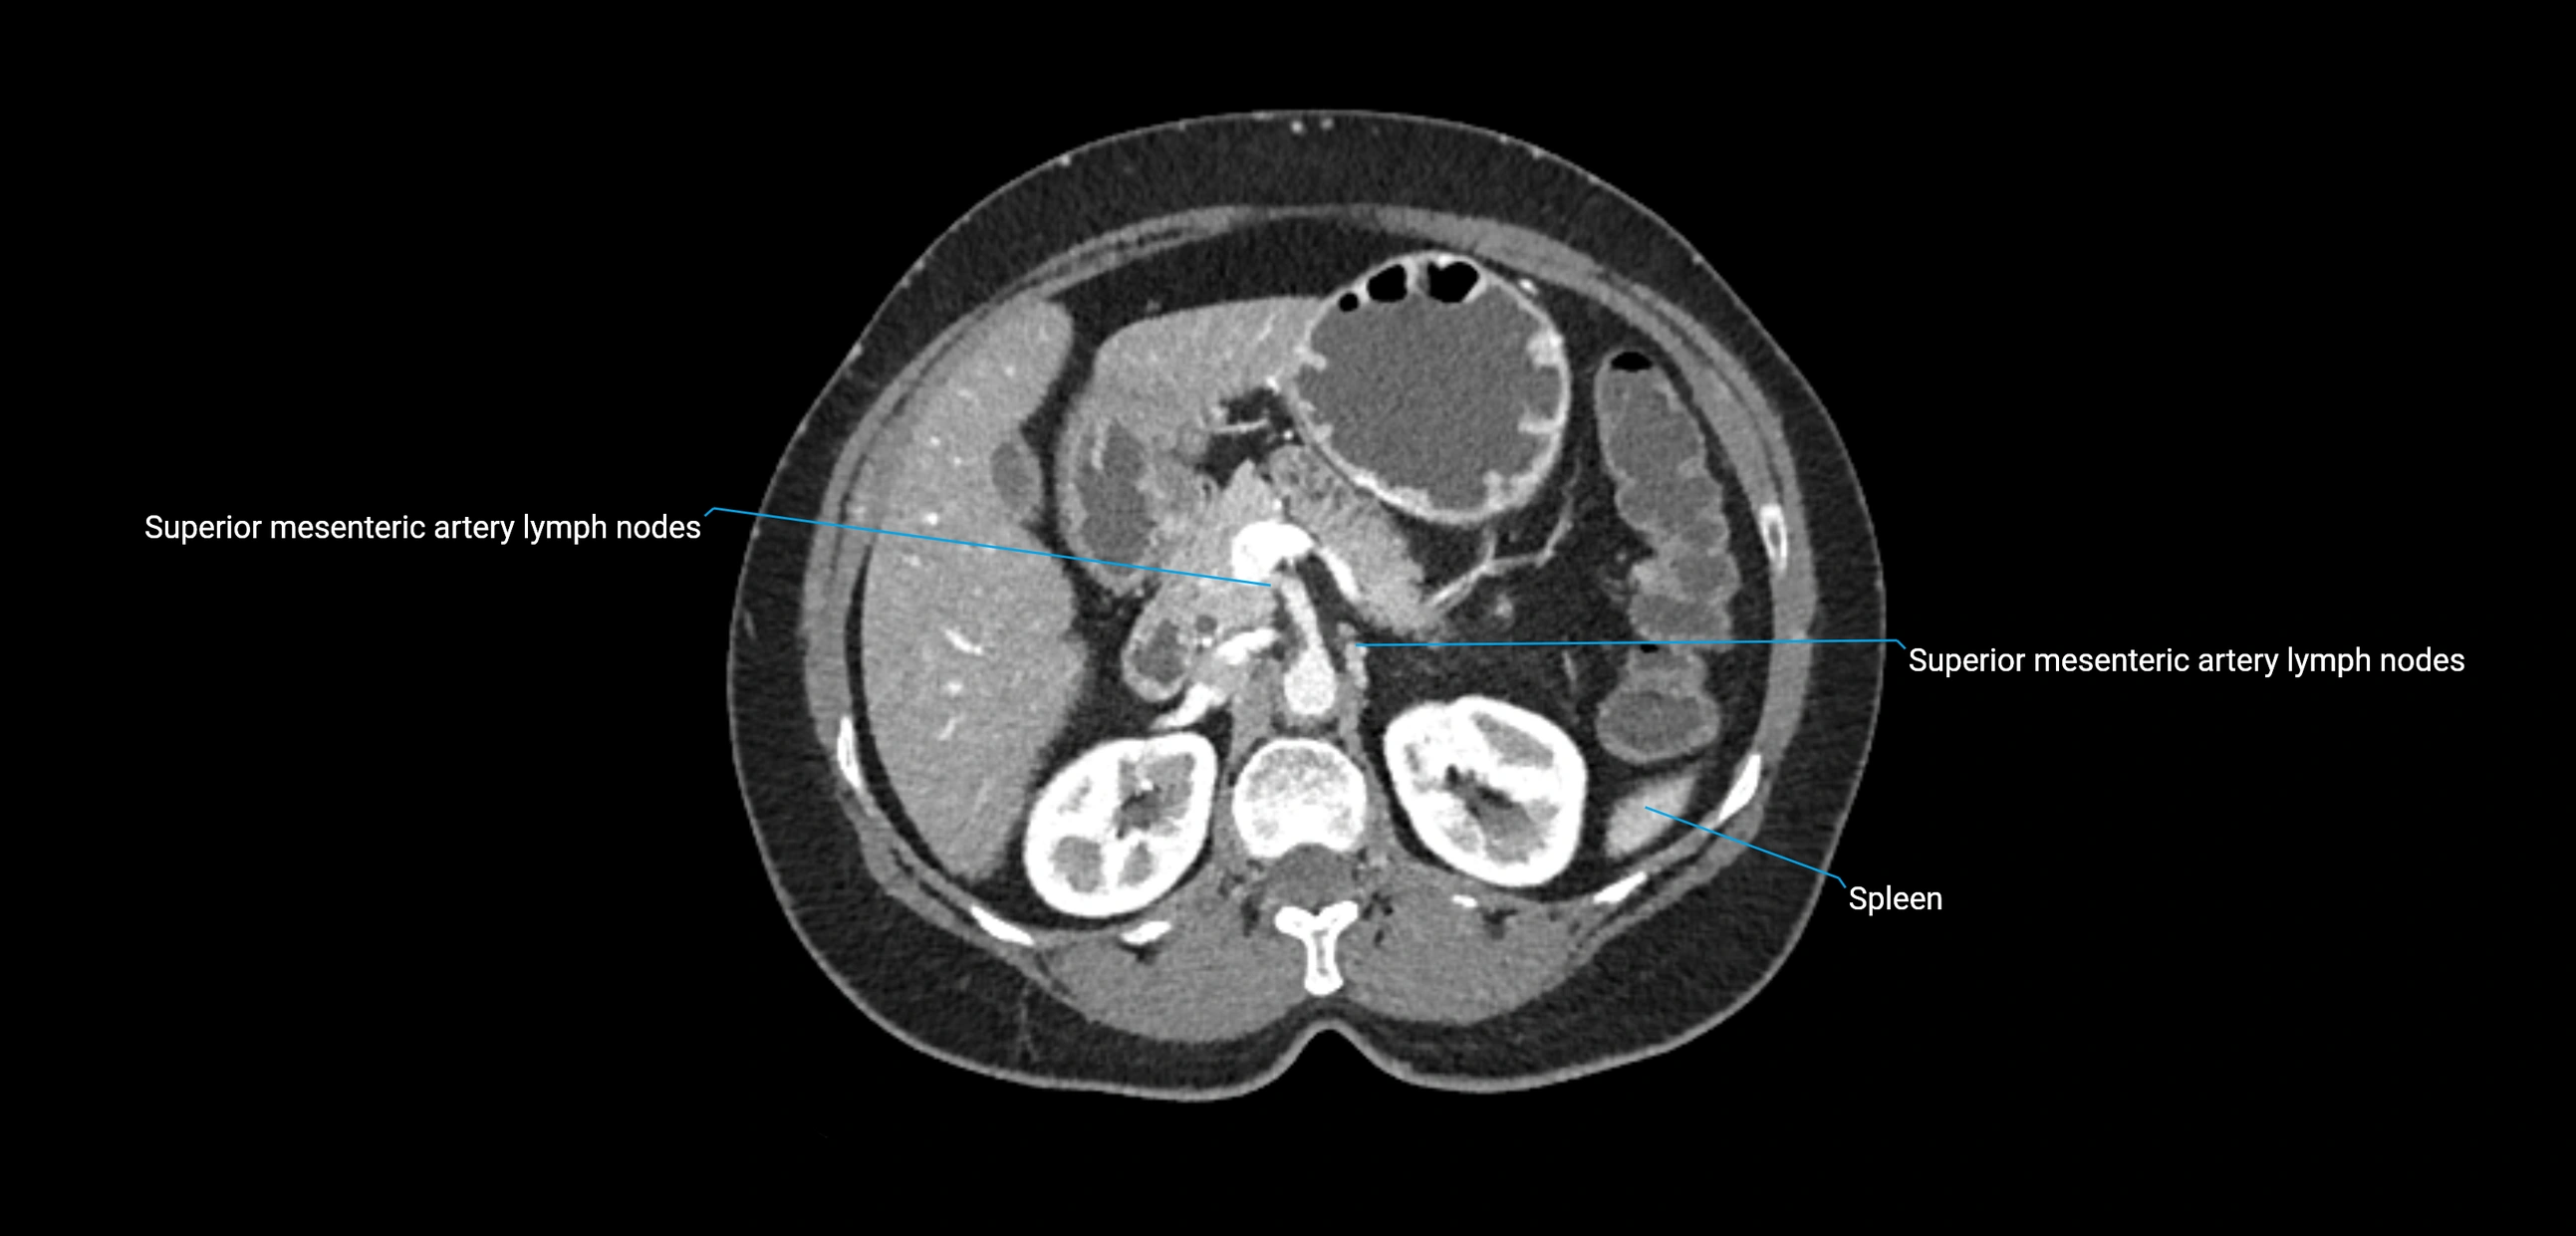

CT Appearance

CT Pre-Contrast:

• Nodes appear as soft-tissue density nodules adjacent to the aorta and IVC

CT Post-Contrast:

• Normal nodes enhance homogeneously

• Malignant nodes may show heterogeneous enhancement, central necrosis, or conglomerate formation

• Size >1 cm short axis is suspicious, though morphology and distribution are equally important